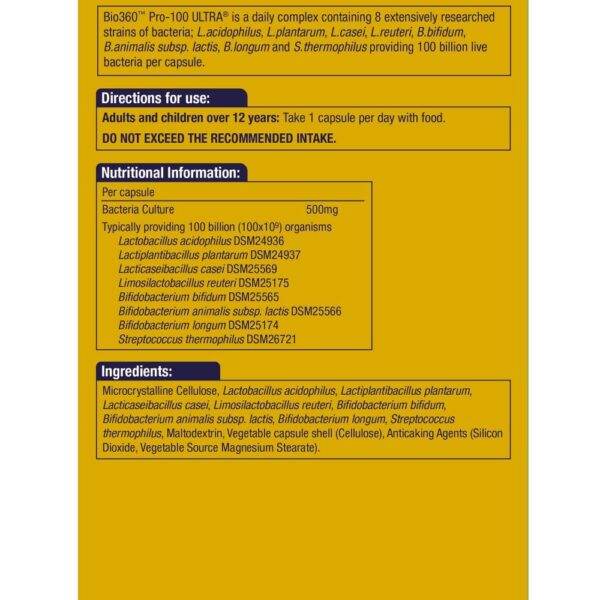

Pro-100 ULTRA je skrbno izbrana mešanica osmih bakterij: Lactobacillus acidophilus, Lacticaseibacillus casei, Limosilactobacillus reuteri, Lactiplantibacillus plantarum, Streptococcus thermophilus, Bifidobacteria lactis, Bifidobacteria longum in Bifidobacteria bifidum.

Pro-100 ULTRA je širokospektralno in zelo močno dnevno dopolnilo z dobrimi bakterijami, saj vsebuje 100 milijard živih bakterij na kapsulo. Zasnovan je tako, da vam zagotovi dopolnilo najvišje moči, ko ga potrebujete.

Pro-100 ULTRA je skrbno izbrana mešanica osmih bakterij: Lactobacillus acidophilus, Lacticaseibacillus casei, Limosilactobacillus reuteri, Lactiplantibacillus plantarum, Streptococcus thermophilus, Bifidobacteria lactis, Bifidobacteria longum in Bifidobacteria bifidum.

Pro-100 ULTRA je širokospektralno in zelo močno dnevno dopolnilo z dobrimi bakterijami, saj vsebuje 100 milijard živih bakterij na kapsulo. Zasnovan je tako, da vam zagotovi dopolnilo najvišje moči, ko ga potrebujete. Po zaključenem tečaju jemanja mikrobnega dodatka Pro-100 Ultra lahko nadaljujete s probiotiki Pro30 MAX ali Ostrovit Pharma.

Vse bakterije, ki jih uporabljamo v naših pripravkih, so človeške rezidenčne bakterije z dokazano sposobnostjo preživetja v prebavilih in učinkovite kolonizacije mikrobioma po zaužitju. Vsi bakterijski sevi, ki jih uporabljamo v vrsti Bio360, so prijazni do veganov in ne potrebujejo hlajenja.

Da bi bili še bolj mirni, lahko zagotovite, da Pro-100 ULTRA ne vsebuje glutena, kvasa, mlečnih izdelkov, soje in oreščkov, zato je primeren za vsak način prehranjevanja.

| Uporaba | Vzemite 1 kapsulo na dan s hrano. Opozorilo: Priporočene dnevne količine oziroma odmerka se ne sme prekoračiti. Prehransko dopolnilo ni nadomestilo za uravnoteženo in raznovrstno prehrano. |

| Sestava | Mikrokristalna celuloza, Lactobacillus acidophilus, Lactiplantibacillus plantarum, Lacticaseibacillus casei, Limosilactobacillus reuteri, Bifidobacterium bifidum, Bifidobacterium lactis, Bifidobacterium longum, Streptococcus thermophilus, maltodekstrin, lupina rastlinske kapsule (celuloza), sredstva proti sprijemanju (silicijev dioksid, magnezijeve soli maščobnih kislin rastlinskega izvora). Ne vsebuje umetnih arom, barvil, konzervansov, laktoze, kvasa in glutena. Vegansko. |